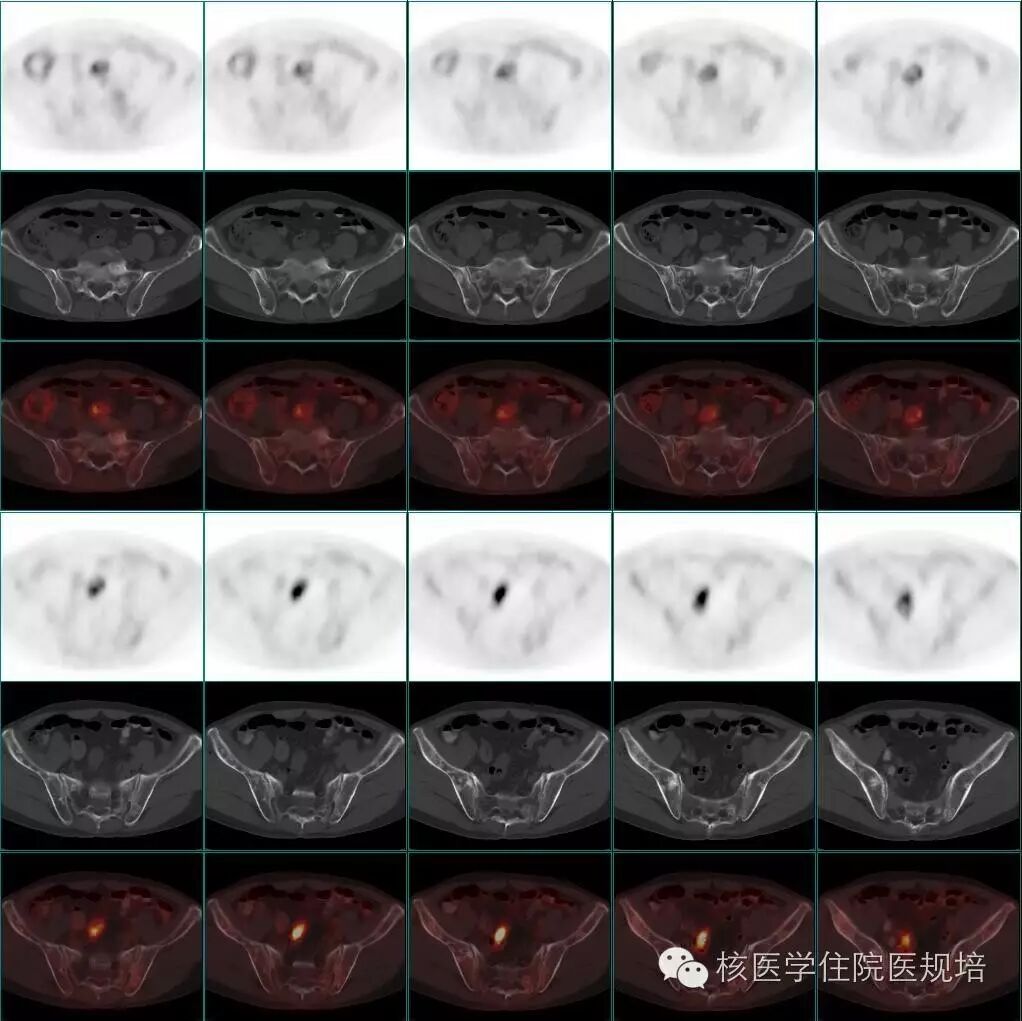

整体观察见MIP图(图3)。主要阳性发现包括:左心房、主动脉及肺动脉主干周围可见环形、弥漫性FDG摄取(SUVmax 3.8),但相应部位平扫CT未见明确异常结构改变(图4);右肾盂扩张,内见形态不规整FDG摄取增高软组织密度肿物影(SUVmax 4.9),边缘毛糙,范围约3.6 cm×2.9 cm×3.0 cm,并包绕上段输尿管,同时见右肾盂积水(图5);四肢长骨FDG摄取对称性增高(SUVmax 3.2),自关节端向骨干伸,相应部位CT见不规则骨质硬化,其中右股骨内侧髁可见溶骨性骨质破坏(图6);脊柱及骨盆亦可见多发性质类似的骨病变(图7、8)。

图6. 四肢长骨对称性FDG摄取增高伴不规则骨质硬化及右股骨内侧髁溶骨性骨质破坏

图7. 脊柱多发骨病变

图8. 骨盆多发骨病变

骨骼受累者约占96%,多为四肢长骨骨干、干骺端对称的成骨性骨质破坏,其中约一半患者可出现骨痛。X线及CT可表现为四肢长骨(下肢为主)骨干、干骺端双侧对称的弥漫性骨质硬化及骨膜炎(如图9),也可表现为溶骨性、混合性骨质破坏及中轴骨病变。ECD的全身骨显像可见四肢骨干、干骺端双侧对称性放射浓聚(如图10)。骨骼病的典型特征对疾病诊断有重要意义。